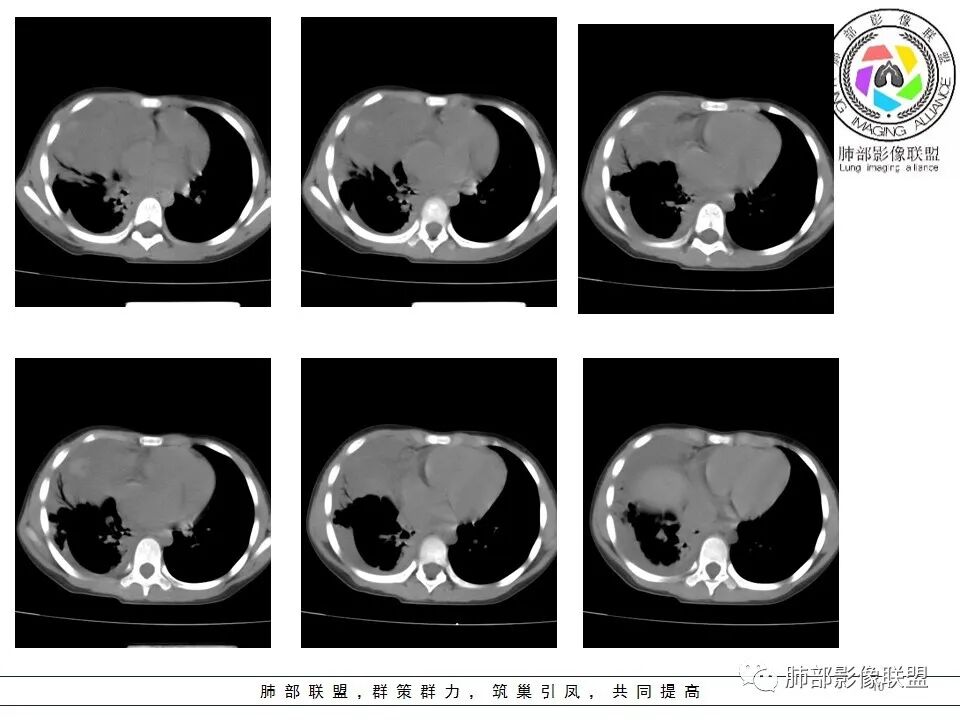

一切∮随缘: 前纵隔偏右侧实性占位,向右肺挤压,右肺膨胀不全,右侧胸水,心包似乎也有胸水,病灶较大无增强,平扫密度欠均匀,内部似可见低密度坏死及高密度钙化影,年轻男性,考虑恶性,生殖细胞肿瘤(精原细胞瘤?恶性畸胎瘤?),鉴别神经母细胞瘤,肺母细胞瘤,PNET?

秦化君: 右前上纵隔软组织密度肿块,边缘部分清晰澎隆,与血管及心包间界线不清,密度较均匀。挤压相邻肺组织形成膨胀不良,侵及胸膜形成胸腔积液。双肺内见随机分布结节。考虑纵隔恶性占位(肺及胸膜转移),生殖细胞瘤,畸胎瘤,淋巴瘤。建议穿刺活检。

放射线 (王秀仙): 右侧前纵膈巨大肿块,与纵膈大血管分界不清并受压,右肺组织受压膨胀不全,密度不均,内可见高密度钙化及低密度坏死区,双肺多发结节状转移灶,右侧胸腔积液,年轻男性,考虑生殖细胞肿瘤,精原细胞瘤可能性大。

宇宙: 男性小孩,右前纵膈不规则肿块,与心脏及大血管分界不清,邻近肺组织受压,其内可见钙化及低密度坏死,两肺多发类圆形结节,右侧胸水,考虑精原细胞瘤伴两肺及胸膜转移,鉴别恶性畸胎瘤。

右前纵隔巨大软组织肿块,主要偏向右侧生长,边界不清,密度不均匀,内见大片状低密度坏死区及散在钙化灶,未见骨骼影及脂肪密度影。、双肺随机分布的转移瘤结节,右肺肺不张及右侧胸腔积液,提示恶性肿瘤病变伴双肺及胸膜转移。